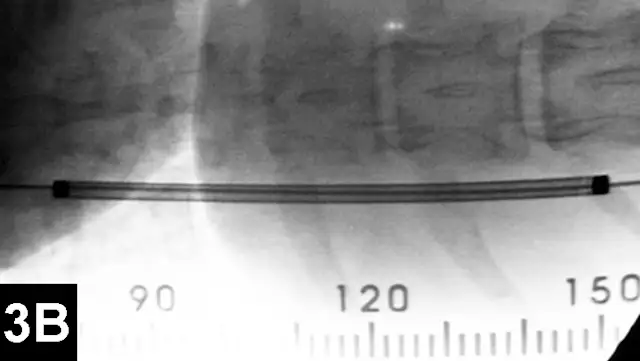

IR techniques that involve placement of an intraluminal stent to alleviate signs associated with malignant obstructions have been described in veterinary patients (Figure 2).5 The author has performed multiple palliative stenting procedures in the urinary tract and upper and lower GI tracts and has relieved luminal obstructions caused by neoplasia or intractable benign strictures in many different sizes of animals, including ferrets.5-11 The IR techniques were fast, safe, and effective. Complications were minor and uncommon.

Figure 2A: Serial lateral positive contrast urethrocystograms in a dog with a malignant urethral obstruction secondary to a prostatic tumor.

Maximal urethral diameters measured using a colonic marker catheter to adjust for radiographic magnification.